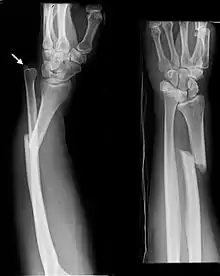

Monteggia Fracture (fracture of proximal ulna)

Galeazzi facture (displaced fracture of the radius)

- Monteggia fracture - a fracture of the near to elbow end of the ulna with the dislocation of the head of the radius at the elbow joint.[2]

- Galeazzi fracture - not a fracture of the ulna but a displaced fracture of the radius accompanied by a dislocation of the ulna at the wrist, where the radius and ulna come together.[2]